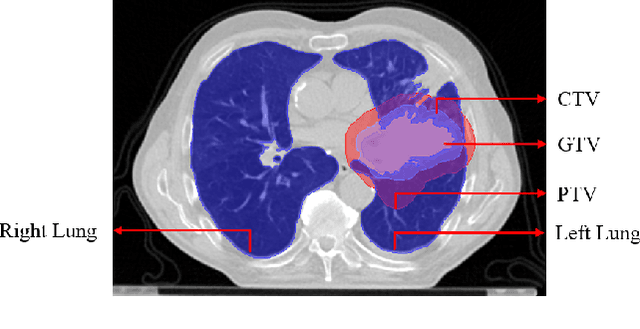

Abstract:Lung cancer is one of the deadliest cancers, and in part its effective diagnosis and treatment depend on the accurate delineation of the tumor. Human-centered segmentation, which is currently the most common approach, is subject to inter-observer variability, and is also time-consuming, considering the fact that only experts are capable of providing annotations. Automatic and semi-automatic tumor segmentation methods have recently shown promising results. However, as different researchers have validated their algorithms using various datasets and performance metrics, reliably evaluating these methods is still an open challenge. The goal of the Lung-Originated Tumor Segmentation from Computed Tomography Scan (LOTUS) Benchmark created through 2018 IEEE Video and Image Processing (VIP) Cup competition, is to provide a unique dataset and pre-defined metrics, so that different researchers can develop and evaluate their methods in a unified fashion. The 2018 VIP Cup started with a global engagement from 42 countries to access the competition data. At the registration stage, there were 129 members clustered into 28 teams from 10 countries, out of which 9 teams made it to the final stage and 6 teams successfully completed all the required tasks. In a nutshell, all the algorithms proposed during the competition, are based on deep learning models combined with a false positive reduction technique. Methods developed by the three finalists show promising results in tumor segmentation, however, more effort should be put into reducing the false positive rate. This competition manuscript presents an overview of the VIP-Cup challenge, along with the proposed algorithms and results.